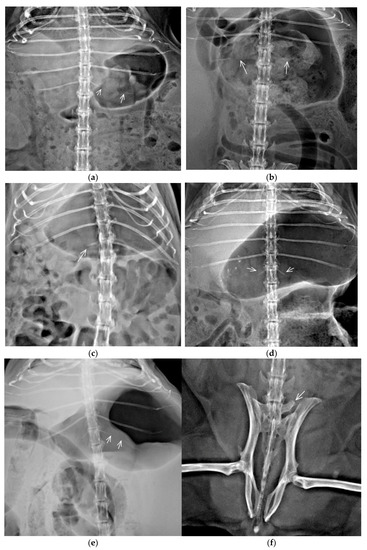

3.2. Congenital Vertebral Anomalies

| TTV | Bilateral incomplete ossification of rib | TL junction | C7/Th13+TTV/L6/S3/Cd7 | 1 | 2.5 | 20 | F |

| TL junction | C7/Th12+TTV/L6/S3/Cd7 | 1 | F | ||||

| TL junction | C7/Th12+TTV/L5/S4/Cd6 | 1 | M | ||||

| TL junction | C7/Th12+TTV/L6/S4/Cd6 | 1 | F | ||||

| TL junction | C7/Th12+TTV/L6/S5/Cd6 | 1 | F | ||||

| TL junction | C7/Th12+TTV/L5/S4/Cd7 | 1 | M | ||||

| Unilateral incomplete ossification of rib | TL junction | C7/Th12+TTV/L5/S4/Cd7 | 2 | 3.33 | 26.67 | F | |

| TL junction | C7/Th12+TTV/L6/S4/Cd6 | 1 | M | ||||

| TL junction | C7/Th12+TTV/L5/S4/Cd6 | 1 | F | ||||

| TL junction | C7/Th12+TTV/L6/S4/Cd7 | 1 | F | ||||

| TL junction | C7/Th13+TTV/L5/S4/Cd6 | 1 | F | ||||

| Bilateral rudimentary rib | TL junction | C7/Th12+TTV/L5/S4/Cd7 | 1 | 1.25 | 10 | F | |

| Unilateral rudimentary rib | TL junction | C7/Th12+TTV/L6/S3/Cd7 | 1 | 1.67 | 13.33 | F | |

| TL junction | C7/Th12+TTV/L6/S4/Cd5 | 1 | M | ||||

| Unilateral rudimentary rib and contralateral incomplete ossification of rib | TL junction | C7/Th12+TTV/L6/S4/Cd6 | 1 | 0.42 | 3.33 | F | |

| LTV | Asymmetrical | LS junction | C7/Th13/L5+LTV/S4/Cd6 | 1 | 2.08 | 16.67 | F |

| LS junction | C7/Th13/L5+LTV/S3/Cd6 | 1 | M | ||||

| LS junction | C7/Th13/L5+LTV/S4/Cd5 | 1 | F | ||||

| LS junction | C7/Th13/L5+LTV/S4/Cd6 | 1 | F | ||||

| LS junction | C7/Th13/L6+LTV/S3/Cd5 | 1 | M | ||||